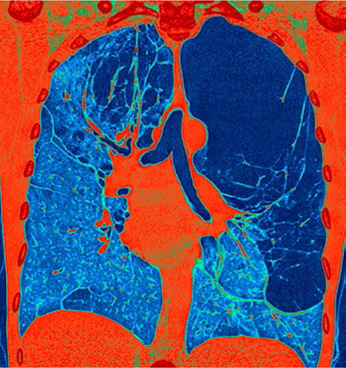

Om er zeker van te zijn dat er sprake is van subcutaan emfyseem wordt er een X-thorax gemaakt. Het is bekend dat er een verhoogde kans is op interstitiële lucht na een bronchoscopie. In dit geval wil de clinicus weten of er lucht aanwezig is op nog andere plaatsen dan subcutaan in de hals. Behalve in de structuren onder de huid kan zich ook lucht bevinden in de pleuraholte, in het mediastinum en in het retroperitoneum. Klinisch is dit moeilijk te bepalen. Maar doordat al deze structuren met elkaar in verbinding staan of slechts gescheiden worden door een kwetsbare en dunne serosa, is de kans erg groot dat zich ook in deze compartimenten lucht bevindt.